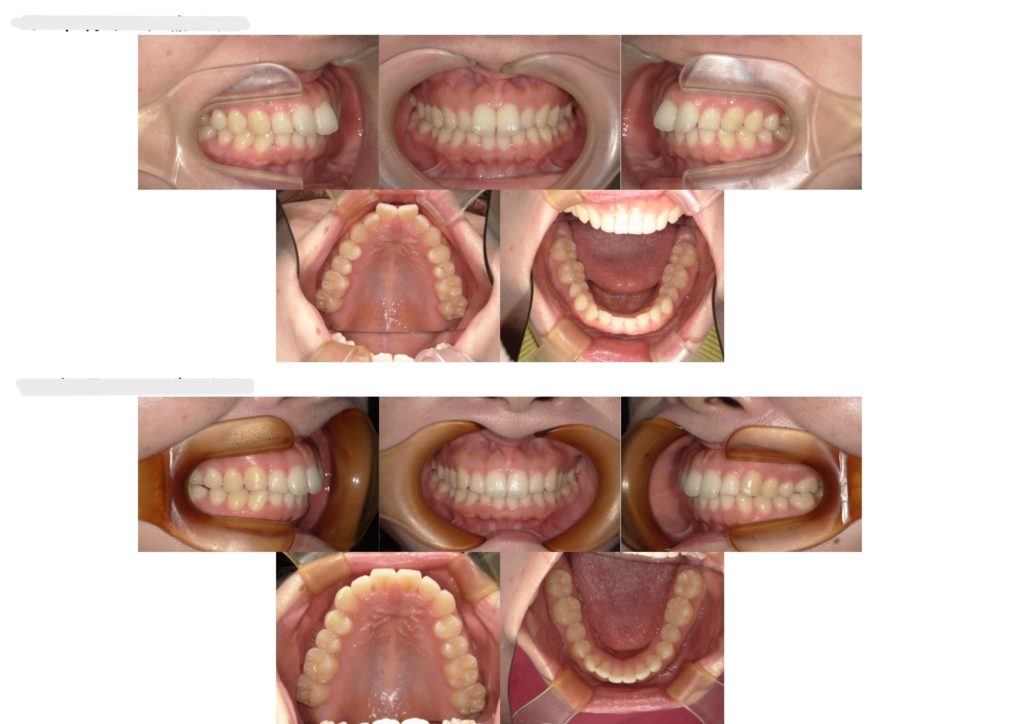

上の写真が治療前、下が治療後のお写真になります。

前歯の捻転が綺麗に並びました!!横から見たときも前歯の出た感じが無くなっていますよね👏🏼しっかり定期的に通っていただきありがとうございました✨

部分矯正の場合は全体を動かすのではなく前歯のみになるので、治療期間も半年ほどの場合が多いです。そのあと保定期間が1年ありますので、トータル1年半~2年程になります。